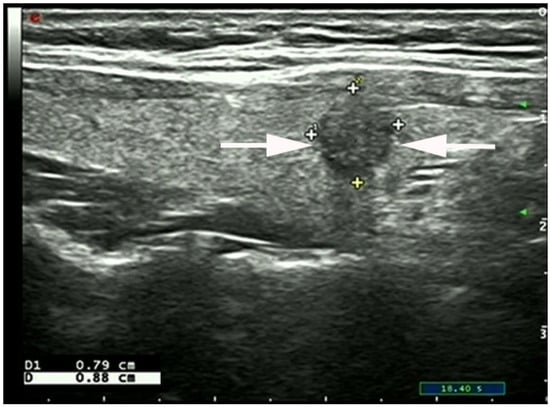

- Chen, S.-P.; Hu, Y.-P.; Chen, B. Taller-Than-Wide Sign for Predicting Thyroid Microcarcinoma: Comparison and Combination of Two Ultrasonographic Planes. Ultrasound Med. Biol. 2014, 40, 2004–2011. [Google Scholar] [CrossRef]

- Kwak, J.Y.; Kim, E.-K.; Youk, J.H.; Kim, M.J.; Son, E.J.; Choi, S.H.; Oh, K.K. Extrathyroid Extension of Well-Differentiated Papillary Thyroid Microcarcinoma on US. Thyroid 2008, 18, 609–614. [Google Scholar] [CrossRef]

- Moon, S.J.; Kim, D.W.; Kim, S.J.; Ha, T.K.; Park, H.K.; Jung, S.J. Ultrasound assessment of degrees of extrathyroidal extension in papillary thyroid microcarcinoma. Endocr Pract. 2014, 20, 1037–1043. [Google Scholar] [CrossRef]

- Chung, S.R.; Baek, J.H.; Choi, Y.J.; Sung, T.Y.; Song, D.E.; Kim, T.Y.; Lee, J.H. Sonographic Assessment of the Extent of Extrathyroidal Extension in Thyroid Cancer. Korean J. Radiol. 2020, 21, 1187–1195. [Google Scholar] [CrossRef]

- Ramundo, V.; Di Gioia, C.R.T.; Falcone, R.; Lamartina, L.; Biffoni, M.; Giacomelli, L.; Filetti, S.; Durante, C.; Grani, G. Diagnostic Performance of Neck Ultrasonography in the Preoperative Evaluation for Extrathyroidal Extension of Suspicious Thyroid Nodules. World J. Surg. 2020, 44, 2669–2674. [Google Scholar] [CrossRef] [PubMed]

- Jeong, S.Y.; Chung, S.R.; Baek, J.H.; Choi, Y.J.; Sung, T.-Y.; Song, D.E.; Kim, T.Y. Sonographic assessment of minor extrathyroidal extension of papillary thyroid micro-carcinoma involving the posterior thyroid capsule. Eur. Radiol. 2022, 32, 6090–6096. [Google Scholar] [CrossRef] [PubMed]

| STCS (n) | 37 | 17 | 0.0002 |

| Anterior capsule involved (n) | 15 | 7 | 0.018 |

| Posterior capsule involved (n) | 22 | 10 | 0.004 |